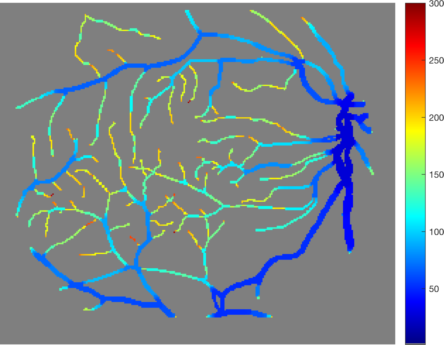

5.6 Segmentation and clustering of biological network structures

In many biological and medical applications network-like structures occur as part of vascular systems. Examples are blood-vessels in retinal images, anisotropic structures in brain or myocardium imaging or at the microscopic level even cells consisting of a round core with several meandering arms of different diameters. Although these networks have a much more complex shape than the examples before, our multiscale method is very useful for a segmentation or clustering of these networks. An example of a round object with "arms" of different diameters is shown in Figure 16 (a). In (b) the corresponding spectral response function is shown and the color-coded segmentation in (c). We can see that the spectral response function has sparse clusters where each cluster corresponds to branches of a certain diameter. Although these "arms" are not eigenfunctions, they do appear in one step and therefore have a distinct scale if they have constant diameter. A similar behavior can be seen in Figure 17. As input for our multiscale method we used a manual blood vessel segmentation (b) of a retinal image (a) from the STARE dataset [HKG00]. The resulting spectral response is shown in Figure 17 (c) and the color-coded segmentation in (d). We see that the different times of appearance of the vessels (indicated by the different colors) lead to a clustering of the underlying network based on the diameter of each branch. With this approach we can get segmentations of the network that contain only branches of certain diameter scales or directly get an estimate of how many different vessel sizes are present and how often they occur. In order to apply our segmentation approach directly on raw retinal images, instead of using it as a postprocessing step, a decomposition method for retinal images similar to Zosso [ZAS+15] could be combined with our multiscale approach.